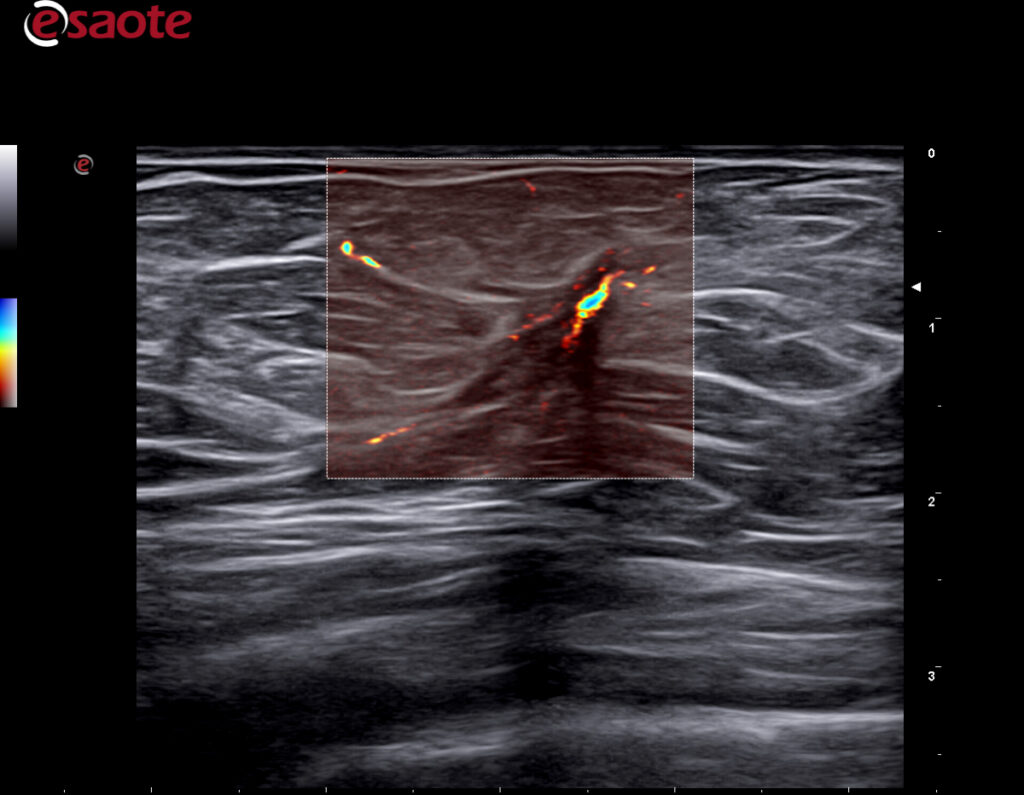

- Supersentiv Doppler og Micro-V

Du ser strukturer tydeligere og mer detaljert enn tidligere. Ultrahøy «framerate» for dynamiske undersøkelser. En super sensitiv og stabil fargedoppler gir en dopplersensitivitet man ikke finner maken til, kombinert med markedets høyeste frekvenser på 25 Mhz. Den nye lineærproben med 4-25Mhz oppløsning, vil bli din nye favoritt. Gir fremragende og markedsledende bildekvalitet på helt overfladiske skanninger, samtidig med premium bildekvalitet ned til 2.5-3.0 cm. Dette er helt enestående for MyLab X90.

Ny bildeoptimaliseringsteknologi; X-View 5.0, fremhever hver eneste piksel, fjerner støy i bildet og forsterker overganger mellom strukturer. Dette gir en utrolig skarphet i bildet og hjelper deg å se hver eneste detalj. M-View 5.0 styrer signalene i flere retninger og legger informasjonen til bildet. Denne utrolige effekten reduserer artefakter og støy i tillegg til å forsterke bildeklarheten. Esaote er kjent for en ekstremt følsom farge – og powerdoppler og leveres nå i tillegg med MicroV. Alle modaliteter kan man styre signalet i ønsket retning, farge og følsomhet. Velg ønsket modul og du vil se mye der du tidligere ikke fikk frem dopplerinformasjon.

MicroV, den nyeste dopplerteknologien fra Esaote med en enestående følsomhet selv i små kar og deteksjon av lave hastigheter. MicroV har en algoritme som helt overlegent separerer bevegelse av væske fra andre bevegelser som skaper forstyrrelser. Dette gir en helt unik dopplerfølsomhet ikke sett tidligere. Med MicroV er det mulig å endre visualiserings algoritmen for å ytterligere forsterke det du ønsker å se.

Kliniske bilder.